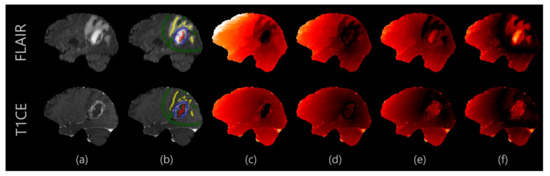

2.2. Proposed Segmentation Algorithm